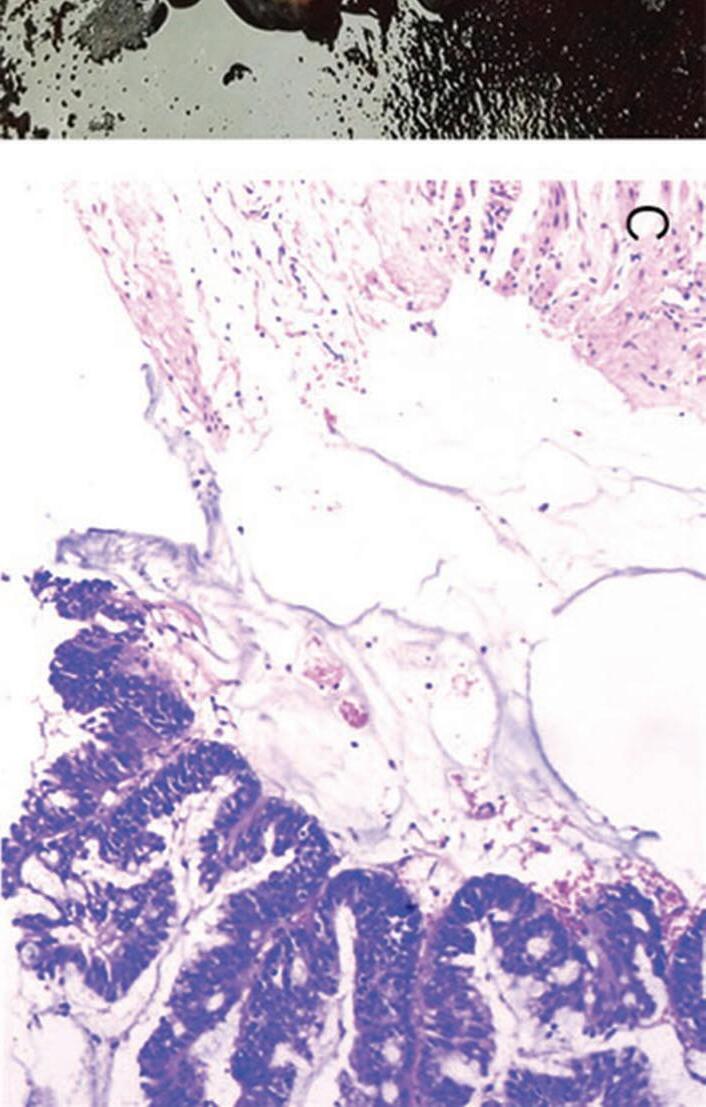

In a 1991 report in The American Journal of Gastroenterology, Drs. Alemayehu and Järnerot challenge prior orthodoxy that colonoscopy is contraindicated in patients with severe ulcerative colitis.